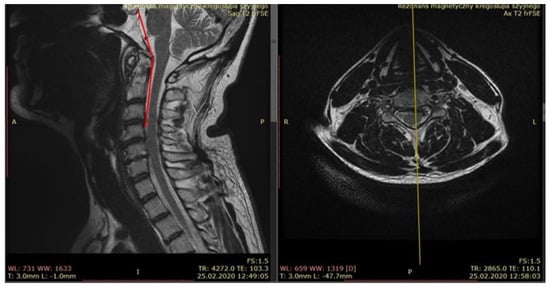

- Clivo-axial angle (CXA), which is the angle between the bony part of the skull base and the posterior part of the C2 dens; a normal range is very wide in the range of 139°–172°, depending on the head position (neutral position is in the range of 150–165°), but an angle below 135° may cause compression of the anterior brainstem and medulla oblongata (Figure 6).